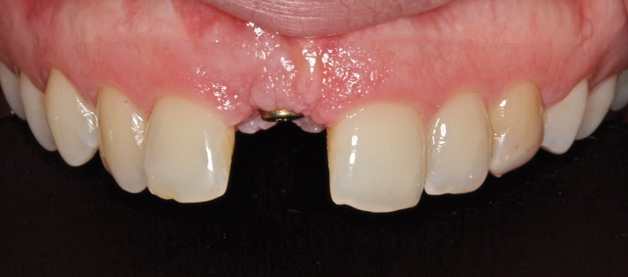

To place an implant without inducing recession, papillae-sparing incisions were created on the mesial and distal of the edentate area at site No. 8. Vertical incisions were made 1 mm away from adjacent teeth and connected with a mid-crestal incision (Figure 13). The extent of the vertical incisions was 3 mm buccally and lingually to expose the alveolar ridge. Horizontal and vertical bone regeneration was clinically confirmed (Figure 14). A 3.3-mm x 12-mm bone level tapered, narrow-connection implant (Straumann, straumann.com) was inserted, and it attained initial primary stability at 25 Ncm (Figure 15 and Figure 16). It was desired to have more than 1 mm of bone buccal and lingual to the implant so as to avoid bone resorption and recession. Then, 4-0 Vicryl single interrupted sutures were used to close the flap (Figure 17).

Fig 14. Clinical confirmation of a 6.4-mm wide ridge.

Figure 14